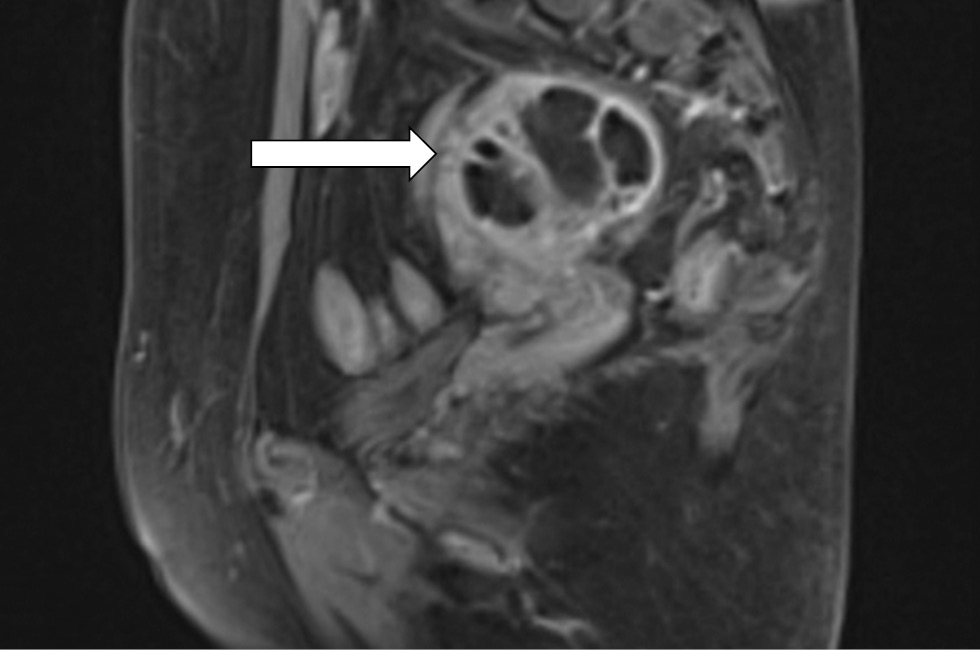

MR-presentation of adenomyosis was concluded based on the magnetic resonance imaging from 06/01/20. Ovarian cancer was questionable, as well as bilateral ovarian endometriomas and lymphadenopathy. Multiple uterine fibroids were of small size (Fig. 3–5).

Fig. 4. Magnetic resonance imaging of the pelvis on admission. The right ovary contains a single-chamber formation with finely dispersed contents (arrow)